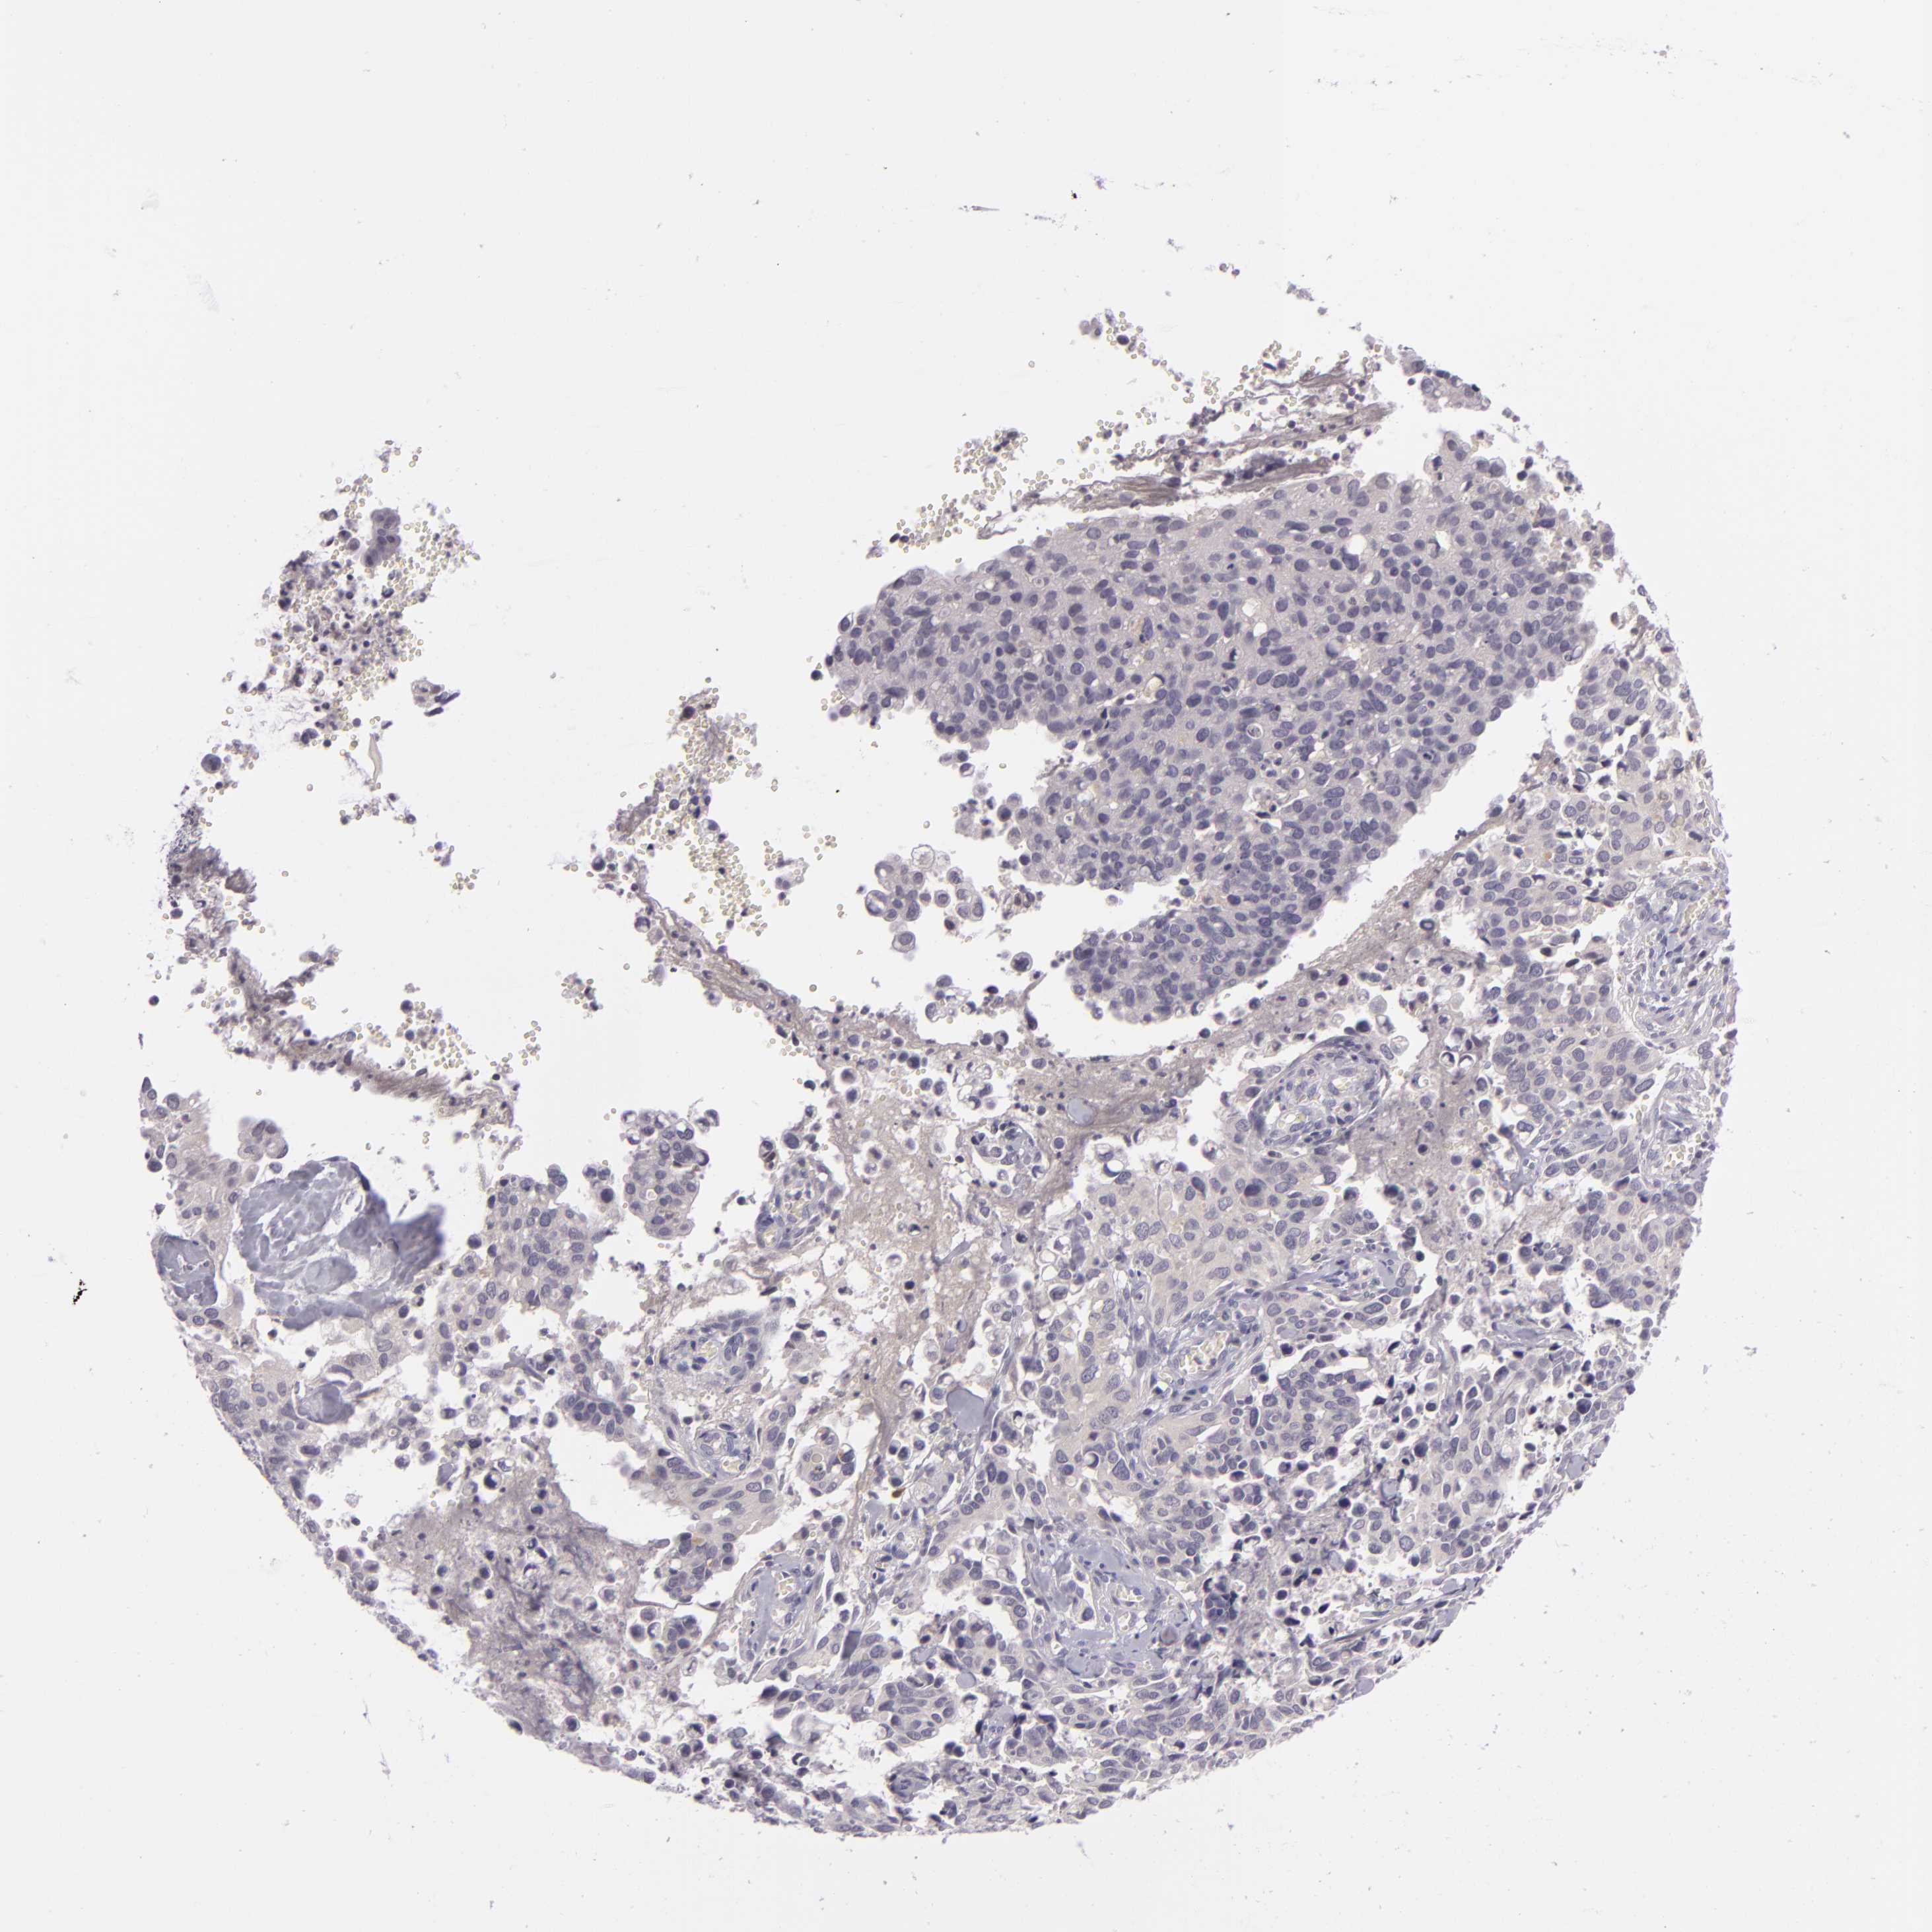

CERVICAL CANCER - Protein expressioni

A mouse-over function shows sample information and annotation data. Click on an image to view it in a full screen mode. Samples can be filtered based on level of antibody staining by selecting one or several of the following categories: high, medium, low and not detected. The assay and annotation is described here.

Note that samples used for immunohistochemistry by the Human Protein Atlas do not correspond to samples in the TCGA dataset.

Antibody stainingi

Antibody staining in the annotated cell types in the current human tissue is reported as not detected, low, medium, or high, based on conventional immunohistochemistry profiling in selected tissues. This score is based on the combination of the staining intensity and fraction of stained cells.

Each image is clickable and will lead to virtual microscopy that enables deeper exploration of all samples and also displays staining intensity scores, fraction scores and subcellular localization as well as patient and tissue information for each sample.

Antibody CAB001960

Antibody CAB016353

Staining

High

Medium

Low

Not detected

Intensity

Strong

Moderate

Weak

Negative

Quantity

>75%

75%-25%

<25%

None

Location

Nuclear

Cytoplasmic/membranous

Cytoplasmic/membranous,nuclear

Adenocarcinoma, NOS

Squamous cell carcinoma, NOS